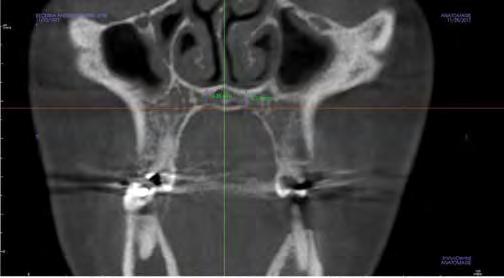

–Corticotomías y Ortodoncia. Ampliando límites del movimiento dental, por la Dra. Aranzazu Senosiain y cols. [50]

–Tratamiento de un caso de Ortodoncia y Cirugía Ortognática con placas preformadas y tecnología 3D, por la Dra. Elena Bonilla Morente y cols. [62]

–Uso del anclaje esqueletal como alternativa eficiente en el manejo ortopédico de clases III por deficiencia de maxilar superior, por el Dr. Carlos Becerra y cols. [74]

–MARPE, una alternativa a la disyunción en el paciente adulto, por el Dr. Enrique Solano y cols. [88]